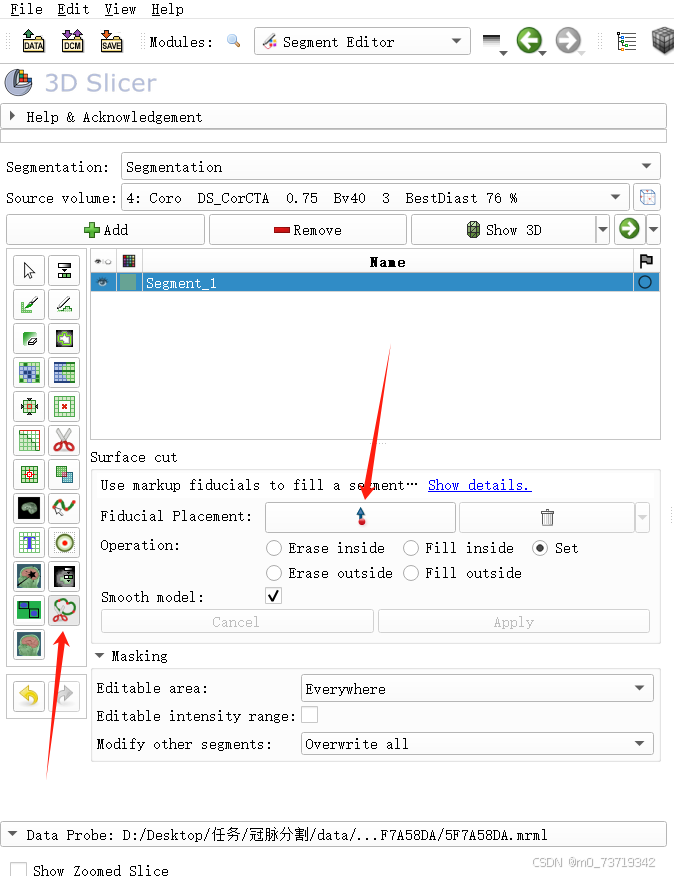

点击segment Editor

点击Add创建第一个标签

依次点击如下按钮

在三个视图中分别圈出心包的位置(注意多圈一些以免血管可能漏,鼠标右键退出圈点功能)如下图所示,可以在三维视图中对圈的范围进行调整

圈完后点击apply完成三维心包分割